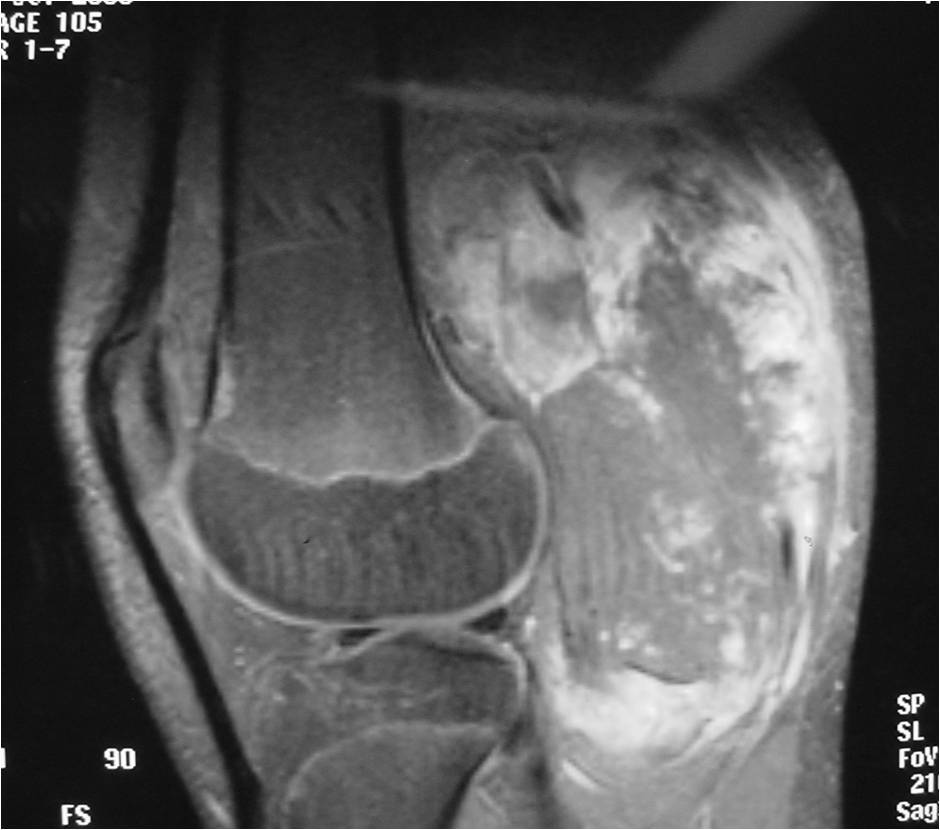

Radiographic Presentation

- Aggressive motheaten to permeative lesion

- Indistinct border in most cases

- Osseous destruction with a soft tissue component

- Chondroid matrix calcification may be present (60-70% of cases)

- Soft tissue mass

- Locally aggressive

- Cortical destruction in approximately half of cases

- Extension of tumor into adjacent soft tissues